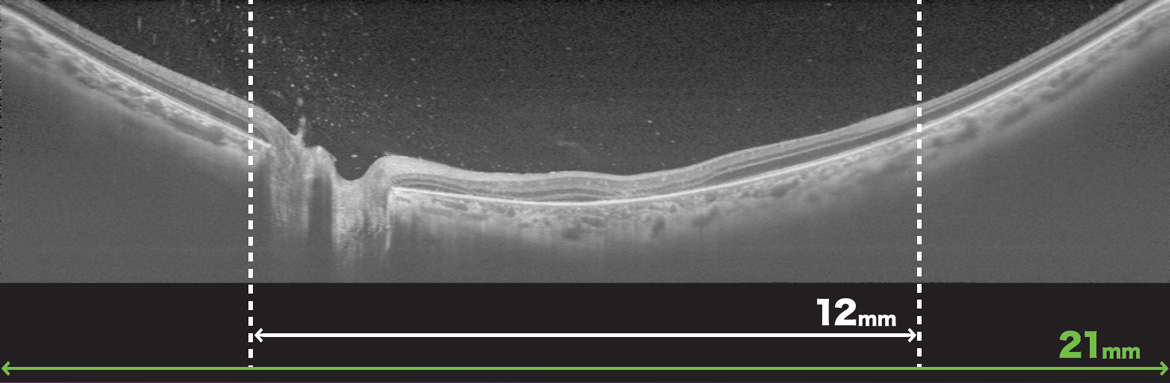

マルチモダルイメージングのTritonが、Triton Proとしてリニューアル。広角OCT撮影用アタッチメントレンズWA-1¹を使用することで、最大21mmのラインスキャン、ラジアルスキャン、OCT-Aが撮影可能になりました。IMAGEnet6にはSmart Denoise機能が追加され、トプコン独自のノイズ除去機能により、3Dを含むB-scanおよびOCT-A画像がより鮮明に描写可能です。

- 広角OCT撮影 最大スキャン幅21mm

別売付属のアタッチメントをつけるだけで簡単に広角撮影が可能です。

21mmのラインスキャン、ラジアルスキャン、5ラインクロススキャン、OCT-A画像が撮影可能です。